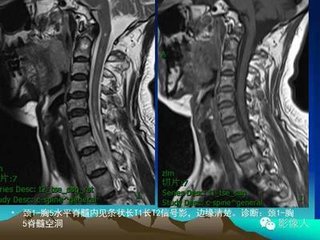

本病的大特点是关节破坏的程度与疼痛不成正比,病人发病后常常因无疼或轻微疼痛而延误就诊时间,造成关节的进一步破坏。后期,由于关节神经营养性差而易造成骨质疏松,负重关节极易出现粉碎性骨折,且疼觉欠敏感。>>>>我有类似症状,请医生帮我诊断一下